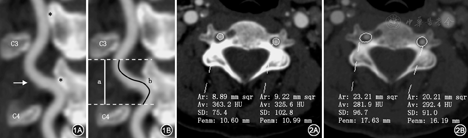

所有患者均经过GE LightSPeed VCT 64排双能CT或者PhiliPs 256i CT进行颈椎增强CT扫描,将增强图像导入Philips IntelliSpace Portal工作站进行三维重建。选取观察组患者扭曲椎动脉相邻节段及对照组各节段的横突孔作为观测对象(图1),采用spline contour作为面积测量工具,在血管窗(窗宽800,窗位300)中测量椎动脉截面积(VA),在骨窗(窗宽1 500,窗位500)中测量横突孔面积(TF) (图2)。为评价单节段内椎动脉扭曲程度,采用屏幕E尺工具测量受试节段上侧横突孔下缘至下侧横突孔上缘的直线距离作为该段颈段长度,测量沿相应节段椎动脉走行所作的曲线长度作为该段椎动脉长度,以后者除以前者作为椎动脉扭曲系数(s)(图1)[5]。以上数据由两名受过培训的临床医师进行测量,数据取两者的均值。如出现两组数据相差超过较小值的5%,则重测数据。

以23.0、28.7 mm2分别作为健康人群C4或C6横突孔平均面积,以7.47、7.63 mm2分别作为C4或C6椎动脉平均面积[6],以横突孔面积或椎动脉截面积大于健康人群平均面积记为(+),对观察组共72例因椎动脉扭曲受累的C4或C6及对照组相同节段颈椎分类计数显示,患者横突孔面积与椎动脉截面积呈正相关,差异有统计学意义(P<0.05)。以扭曲系数>1.06计为(+),分析C4与C6横突孔面积与椎动脉扭曲系数的相关性,横突孔面积与椎动脉扭曲系数同样呈正相关。椎动脉扭曲是横突孔扩大的诱发因素(表2,表3、图3)。